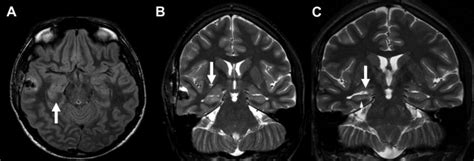

Diagnosing NMDAR Encephalitis can be challenging, as the symptoms are often non-specific and can be similar to those of other conditions. A diagnosis is typically made based on a combination of: * Clinical evaluation, including a physical exam and medical history * Laboratory tests, including blood tests and cerebrospinal fluid analysis * Imaging studies, such as MRI or CT scans Treatment for NMDAR Encephalitis usually involves a combination of: * Immunotherapy, such as corticosteroids, intravenous immunoglobulin, or plasmapheresis * Tumor removal, if a tumor is present * Symptomatic treatment, including medications to manage seizures, psychiatric symptoms, and other symptoms